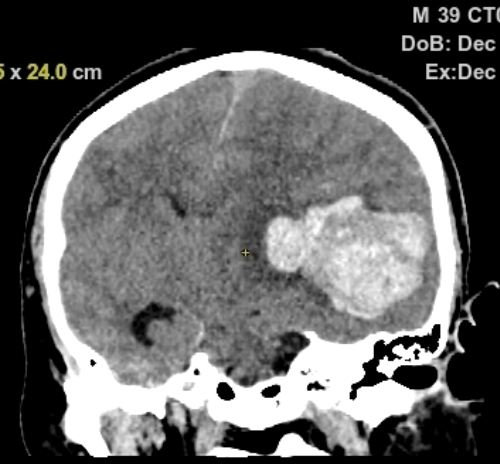

急诊头部CT显示左颞顶巨大脑内血肿,中线结构移位,脑疝

头部CTA提示:左颞顶AVM合并大脑中远端动脉瘤